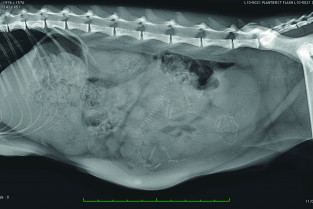

Les pièges de la reproduction au travers de cas cliniques